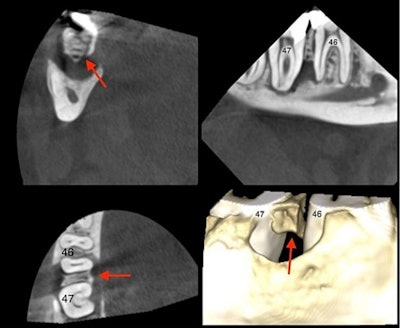

The CBCT revealed the presence of sequestered bone between tooth #46 and tooth #47 (red arrow). The sequester is shown in coronal, sagittal, and axial views as well as in a 3D reconstructed view.

To treat him, tooth #47 was removed and a sequestrectomy was performed under local anesthesia. During the procedure, a loose, nonbleeding fragment of necrotic bone, which was detached and isolated from the healthy bone by a layer of granulated tissue, was discovered. A small groove was noted, which was likely to be the original drill hole that was created when the intraosseous anesthesia injection was administered during the deep cavity treatment, they wrote.

Necrotic interdental septum with trajectory of the needle clearly visible (red arrow).